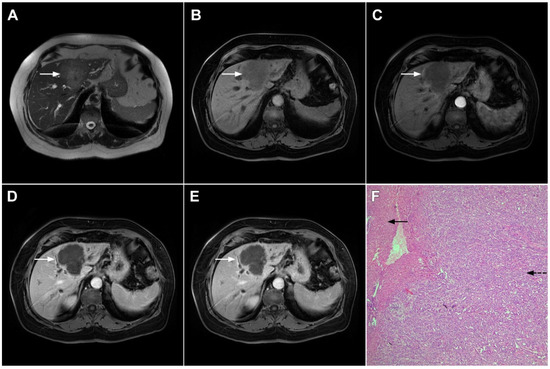

Scirrhous HCC is a rare variant of HCC characterized by rich intralesional fibrotic stroma with incidence of 4.6% among all HCC cases [76]. Scirrhous HCCs are usually seen in MRI scans as lobulated T1-weighted hypointense lesions with a heterogeneous signal intensity on T2-weighted images [77]. With regard to its vascular behavior, Kim et al. showed that the most common enhancement pattern was a peripheral rim-like enhancement in the arterial phase with a progressive central enhancement in the portal–venous and equilibrium phase, which is indistinguishable from mICC (Figure 17) [78]. Moreover, in previous studies washout was seen in only 19% of scirrhous HCC, in comparison to 99.7% of typical HCCs [78]. In addition, similarly to mICC, scirrhous HCC may also cause capsular retraction if it is subcapsular [79]. With regard to the targetoid appearance in the DWI and hepatobiliary phase, both mICC and scirhous HCC can display these imaging features [80]. Therefore, differentiation between scirrhous HCC and mICC represents a real diagnostic challenge, since both lesions have rich fibrous stroma, similar postcontrast behavior, and occur in cirrhotic livers [77]. Concerning different treatment strategies for these tumors, preoperative distinction is very important. In this context, the ancillary feature favoring the diagnosis of mICC include peripheral biliary dilatation, while the presence of a capsule suggests scirrhous HCC [77]. Moreover, the presence of part of the tumor enhancing avidly in the arterial phase favors the diagnosis of scirrhous HCC over mICC [80]. Additionally, Choi SY et al. have shown that mICC more frequently showed T2-weighted central brightness due to the presence of internal necrosis or mucin accumulation [79]. Nevertheless, if the lesion with imaging features of both scirrhous HCC and mICC is seen in the setting of chronic liver disease, according to the Liver Imaging Reporting and Data System (LI-RADS) it is characterized as LI-RADS M and further biopsy is required [81].

Figure 17.

Scirrhous hepatocellular carcinoma in a 68-year-old woman. The axial T2-weighted image (A) shows a moderately hyperintense subcapsular-located lesion in liver segments VI and V (arrow). Note also the capsular retraction. The tumor (arrow) is hypointense in the plain T1-weighted FS image (B), with ring enhancement in the arterial phase (C) and slight progressive central enhancement in the portal venous (D) and delayed phases (E). Hematoxylin and eosin (H&E) staining showed hepatocellular carcinoma (arrow) and normal liver parenchyma adjacent to the tumor (dashed arrow); original magnification ×40 (F).